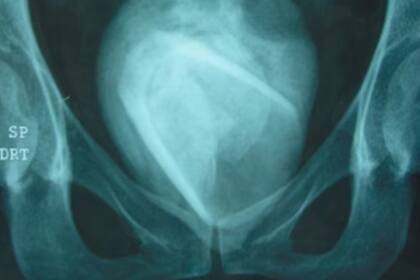

Una insólita situación ocurrió en Sfax, Túnez, cuando una mujer fue a hacerse una consulta por problemas urinarios. Después de una serie de análisis, los médicos que la atendieron encontraron un objeto que la mujer se había introducido hace años en la uretra y quedó alojado. Las imágenes son impactantes y el hecho sorprendió a la comunidad médica.

Al hacerle estudios, los médicos descubrieron que se había formado un cálculo de ocho centímetros de ancho. Asombrados por este hallazgo, luego de la intervención pertinente descubrieron que en su interior había un vaso. Según contó la paciente, se había introducido el objeto hace cuatro años y la piedra estuvo allí durante todo ese tiempo, según fue publicado en Urology Case Reports.

El enorme tamaño del cálculo no pasó para nada desapercibido, sobre todo si se tiene en cuenta que usualmente no son visibles para el ojo humano sin el uso de algún artefacto. Según reveló la paciente, se había introducido el vaso en la uretra hace cuatro años como parte de un juego sexual. Increíblemente, quedó alojado allí y nunca fue a que se lo extrajeran en todo ese tiempo.

Para retirarlo del cuerpo, se realizó una cistolitotomía y se pudo quitar el cálculo exitosamente. Luego de dos días de recuperación posoperatoria, la mujer fue dada de alta y volvió a su hogar sin inconvenientes.